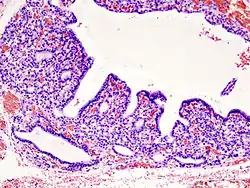

.jpg)

Da die Hyperthyreose durch ein Übermaß an Schilddrüsenhormonen definiert ist, spielt neben Anamnese, klinischen Symptomen und bildgebenden Verfahren (insbesondere Sonographie und Szintigraphie) die Labordiagnostik die entscheidende Rolle. Da die klinischen Symptome jedoch andererseits nicht immer mit nachweislichen Laborveränderungen korrelieren, können zum einen auch beschwerdefreie Patienten pathologisch veränderte Messwerte aufweisen und zum anderen bereits bei moderaten Veränderungen lebensbedrohliche Zustände auftreten; deshalb wurde, um die Wahrscheinlichkeit, dass eine thyreotoxische Krise vorliegt, laborwertunabhängig einschätzen zu können, der Burch-Wartofsky-Score[28] entwickelt.